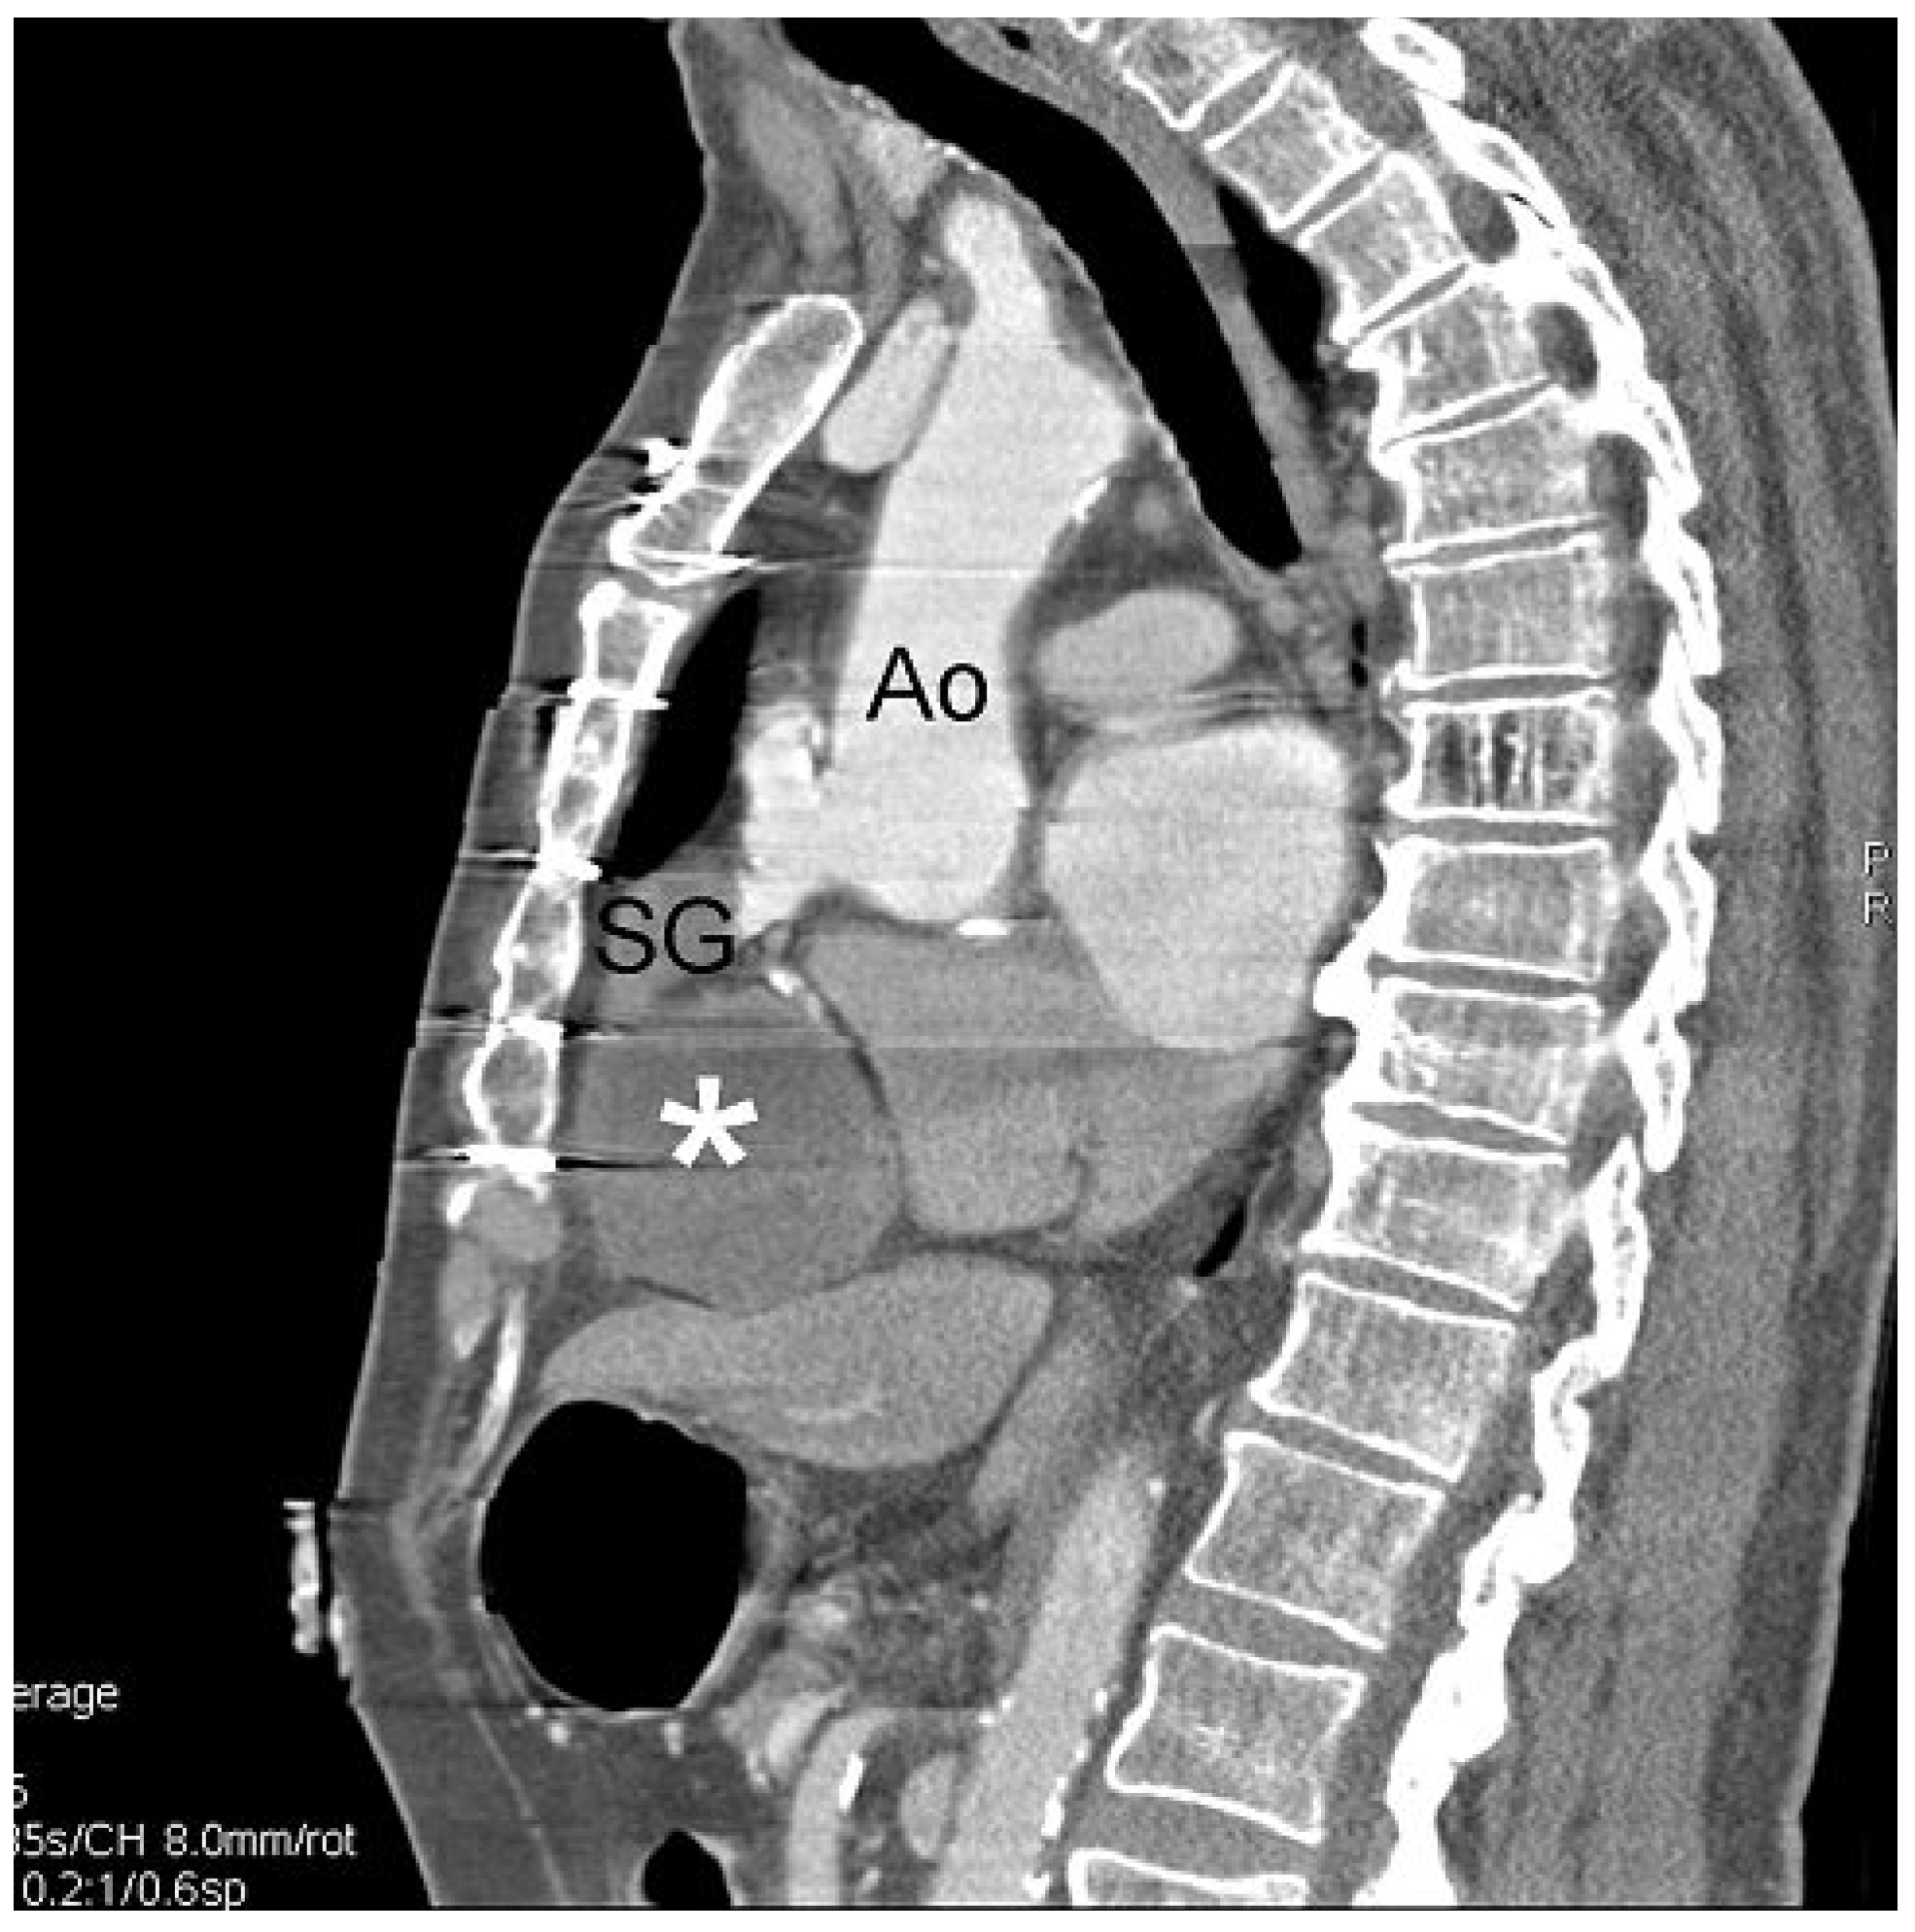

A Giant Saphenous Vein Graft Aneurysm Compressing the Right Cavities